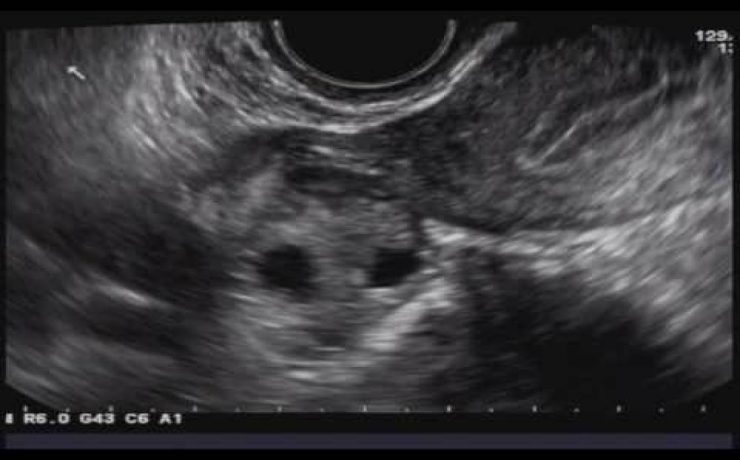

Las vías biliares intrahepática transcurren adyacentes a las raíces de la vena porta y las ramas de la arteria hepática. Los conductos hepáticos derecho e izquierdo se unen para formar el conducto hepático común a nivel del hilio hepático, el cual mide aproximadamente 30mm de longitud y se une al